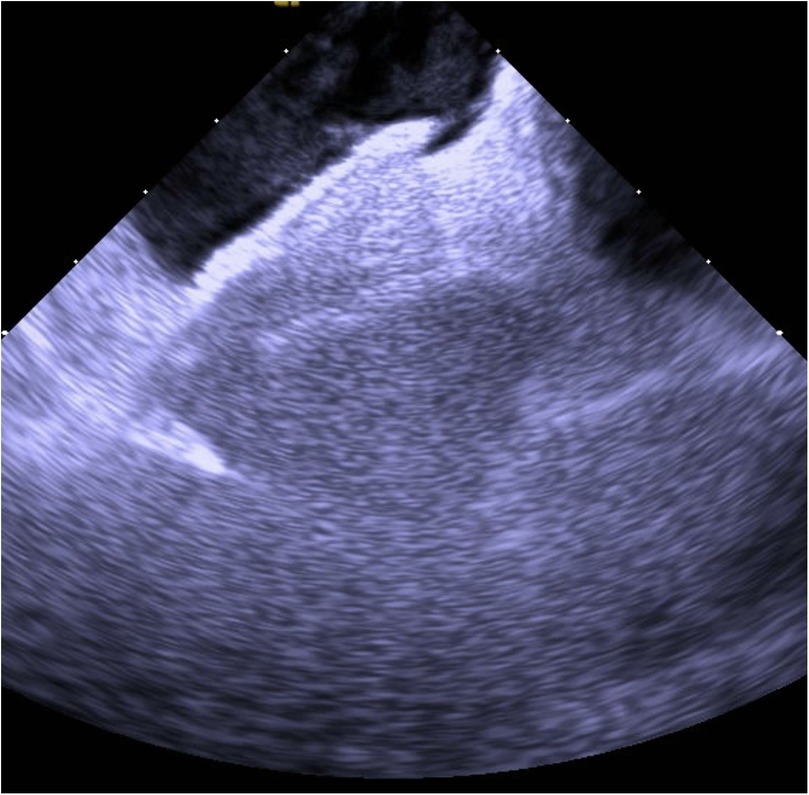

An 80-year-old man presented with progressive dyspnea and severe hypoxemia refractory to high-flow oxygen therapy, ultimately found to have a large persistent patent foramen ovale (PFO) mediated right-to-left-shunt (RTLS). The patient underwent successful percutaneous PFO closure via a 35 mm Amplatz septal occluder guided by intracardiac echocardiography (ICE), resulting in complete resolution of the patient's hypoxia within 24 hours. This case highlights the workup of systemic refractory hypoxemia, the importance of cardiac shunt physiology in considering a RTLS, and the utility of PFO closure under ICE-guidance. For patients with a PFO-mediated RTLS, percutaneous closure offers an effective therapeutic option.